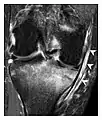

Figure 1: A 56-year-old woman presenting with left knee pain after a fall. (a) Initial anteroposterior radiograph was considered normal, however, subtle cortical disruption of the anterior rim of the medial tibial plateau, medial to the tibial spine, is noted (arrow). (b) Coronal T1-weighted MRI confirms the cortical disruption (arrow) and shows extensive fracture through the proximal tibia. (c) Coronal proton density-weighted image with fat saturation shows extensive edema in the subchondral bone. Note also hypersignal adjacent to the medial collateral ligament corresponding to a grade I sprain (arrowheads).[1]